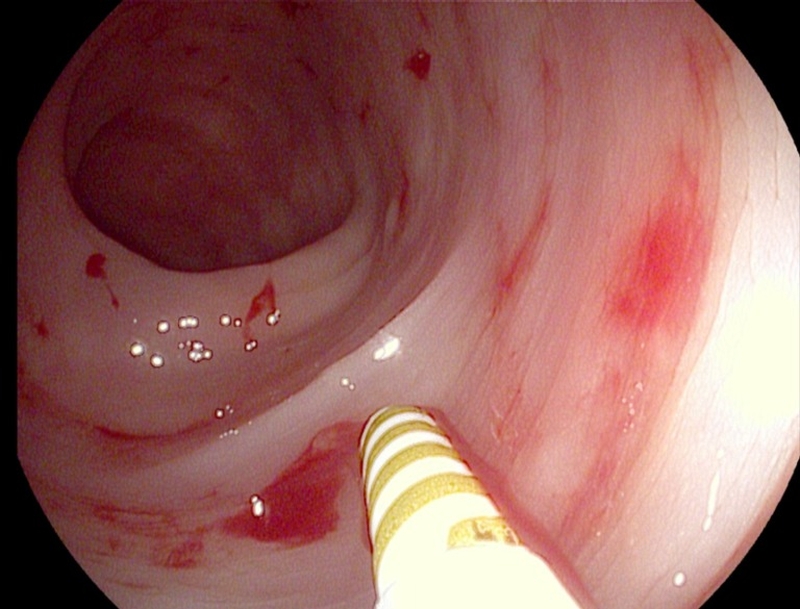

Xuất huyết tiêu hóa là triệu chứng chảy máu do tổn thương ở đường tiêu hóa bao gồm thực quản, ruột non, dạ dày, ruột già hoặc ruột kết, trực tràng, hậu môn bị chảy máu do một tổn thương nào đó.

Nếu xuất huyết xảy ra ở thực quản, dạ dày hoặc phần đầu của ruột non (tá tràng), nó được gọi là chảy máu đường tiêu hóa trên. Nếu chảy máu ở phần dưới của ruột non, ruột già, trực tràng hoặc hậu môn, nó được gọi là chảy máu đường tiêu hóa dưới.